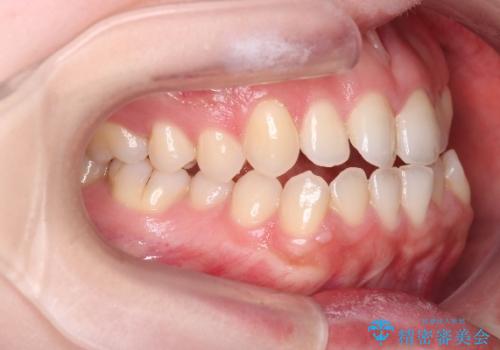

【オープンバイト】前歯のがたがたをなおしたい。

- 笑った時の前歯の見た目が気になることを主訴に来院されました。

上の歯が下の前歯を少し隠すぐらいを目指し、インビザラインにて治療を行いました。